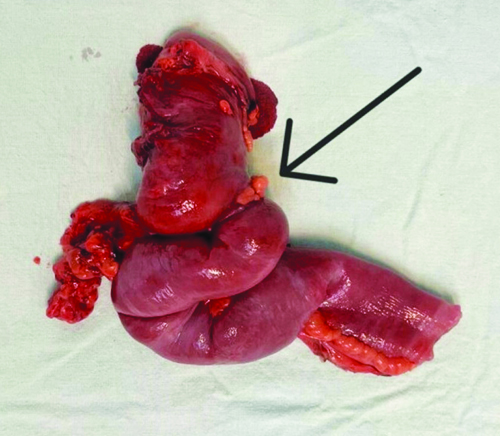

The patient was planned for exploratory laparotomy with ileocolic anastomosis. Intraoperative findings showed a normal omentum, but a thickened and fibrotic stricture mass was palpated at the ileocolic junction, encompassing the terminal ileum, cecum and a portion of the ascending colon. The mass was adherent to the retroperitoneum and positioned over the abdominal aorta. Tissue suspected to be adherent to the aorta was sent for histopathological analysis, which was indicative of a potential infective etiology. Based on the surgeons’ intraoperative expertise and clinical diagnosis, the ileoileal mass was resected with sufficient margins, followed by ileocolic anastomosis [Table/Fig-2,3].

Intraoperative specimen delivered out showing ileoileal stricture.

The resected specimen, measuring 25 centimetres in length, was sent for histopathological study, revealing features consistent with a well-differentiated Neuroendocrine Tumour (NET) of carcinoid type 1. The tumour was found to invade the visceral peritoneum (serosa) and exhibited a mitotic count ranging from 2 to 20 per cubic millimetre. Pathological Tumour, Node Metastasis (TNM) staging classified it as Tumour stage 4, lymph Node nil, Metastasis nil (pT4 NxMx), corresponding to AJCC stage IIIA, as per the clinical updates by Chauhan A et al., 2024 [Table/Fig-4,5] [1].

Resected specimen of small intestine cecum and ascending colon with adequate margins.